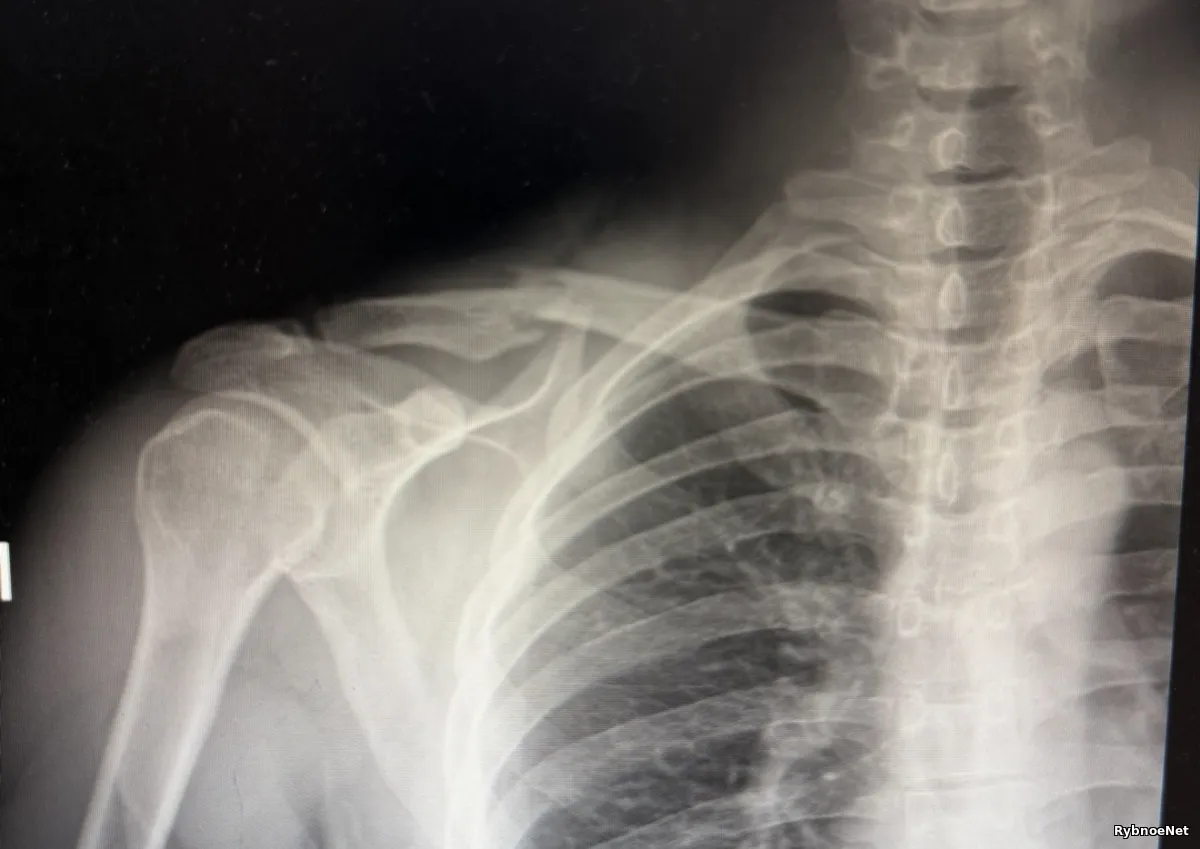

Пострадавшего доставили в областную клиническую больницу, где ему поставили диагноз — перелом ключицы со смещением, повреждение правого плеча. Мужчине предстоит операция и длительное восстановление.

Сейчас он проходит дополнительную диагностику, включая анализы и компьютерную томографию. По предварительным данным, мужчине потребуется хирургическое вмешательство и длительный период реабилитации.